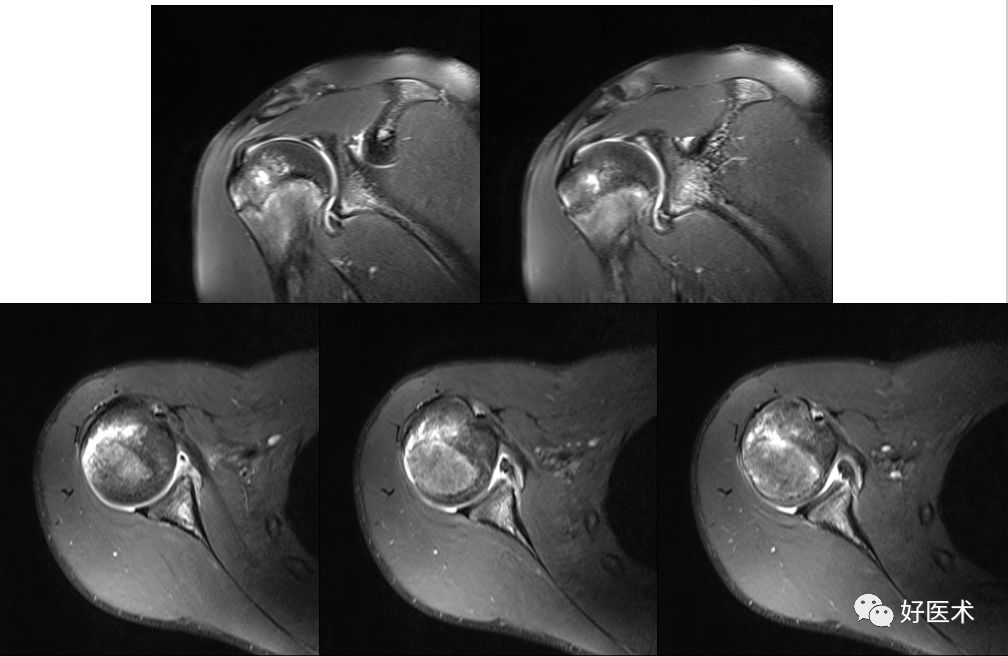

Hill-Sachs损伤

-

Hill-Sachs损伤:肩关节前脱位时,肱骨头撞向关节盂缘可导致肱骨头的后外侧的嵌插骨折

MR间接关节造影1.5T轴位T1W脂肪抑制

MR间接关节造影1.5T冠状面T1W脂肪抑制

Hill-sachs,Bankart,关节囊损伤

SLAP、Bankart合并Hill-Sach损伤